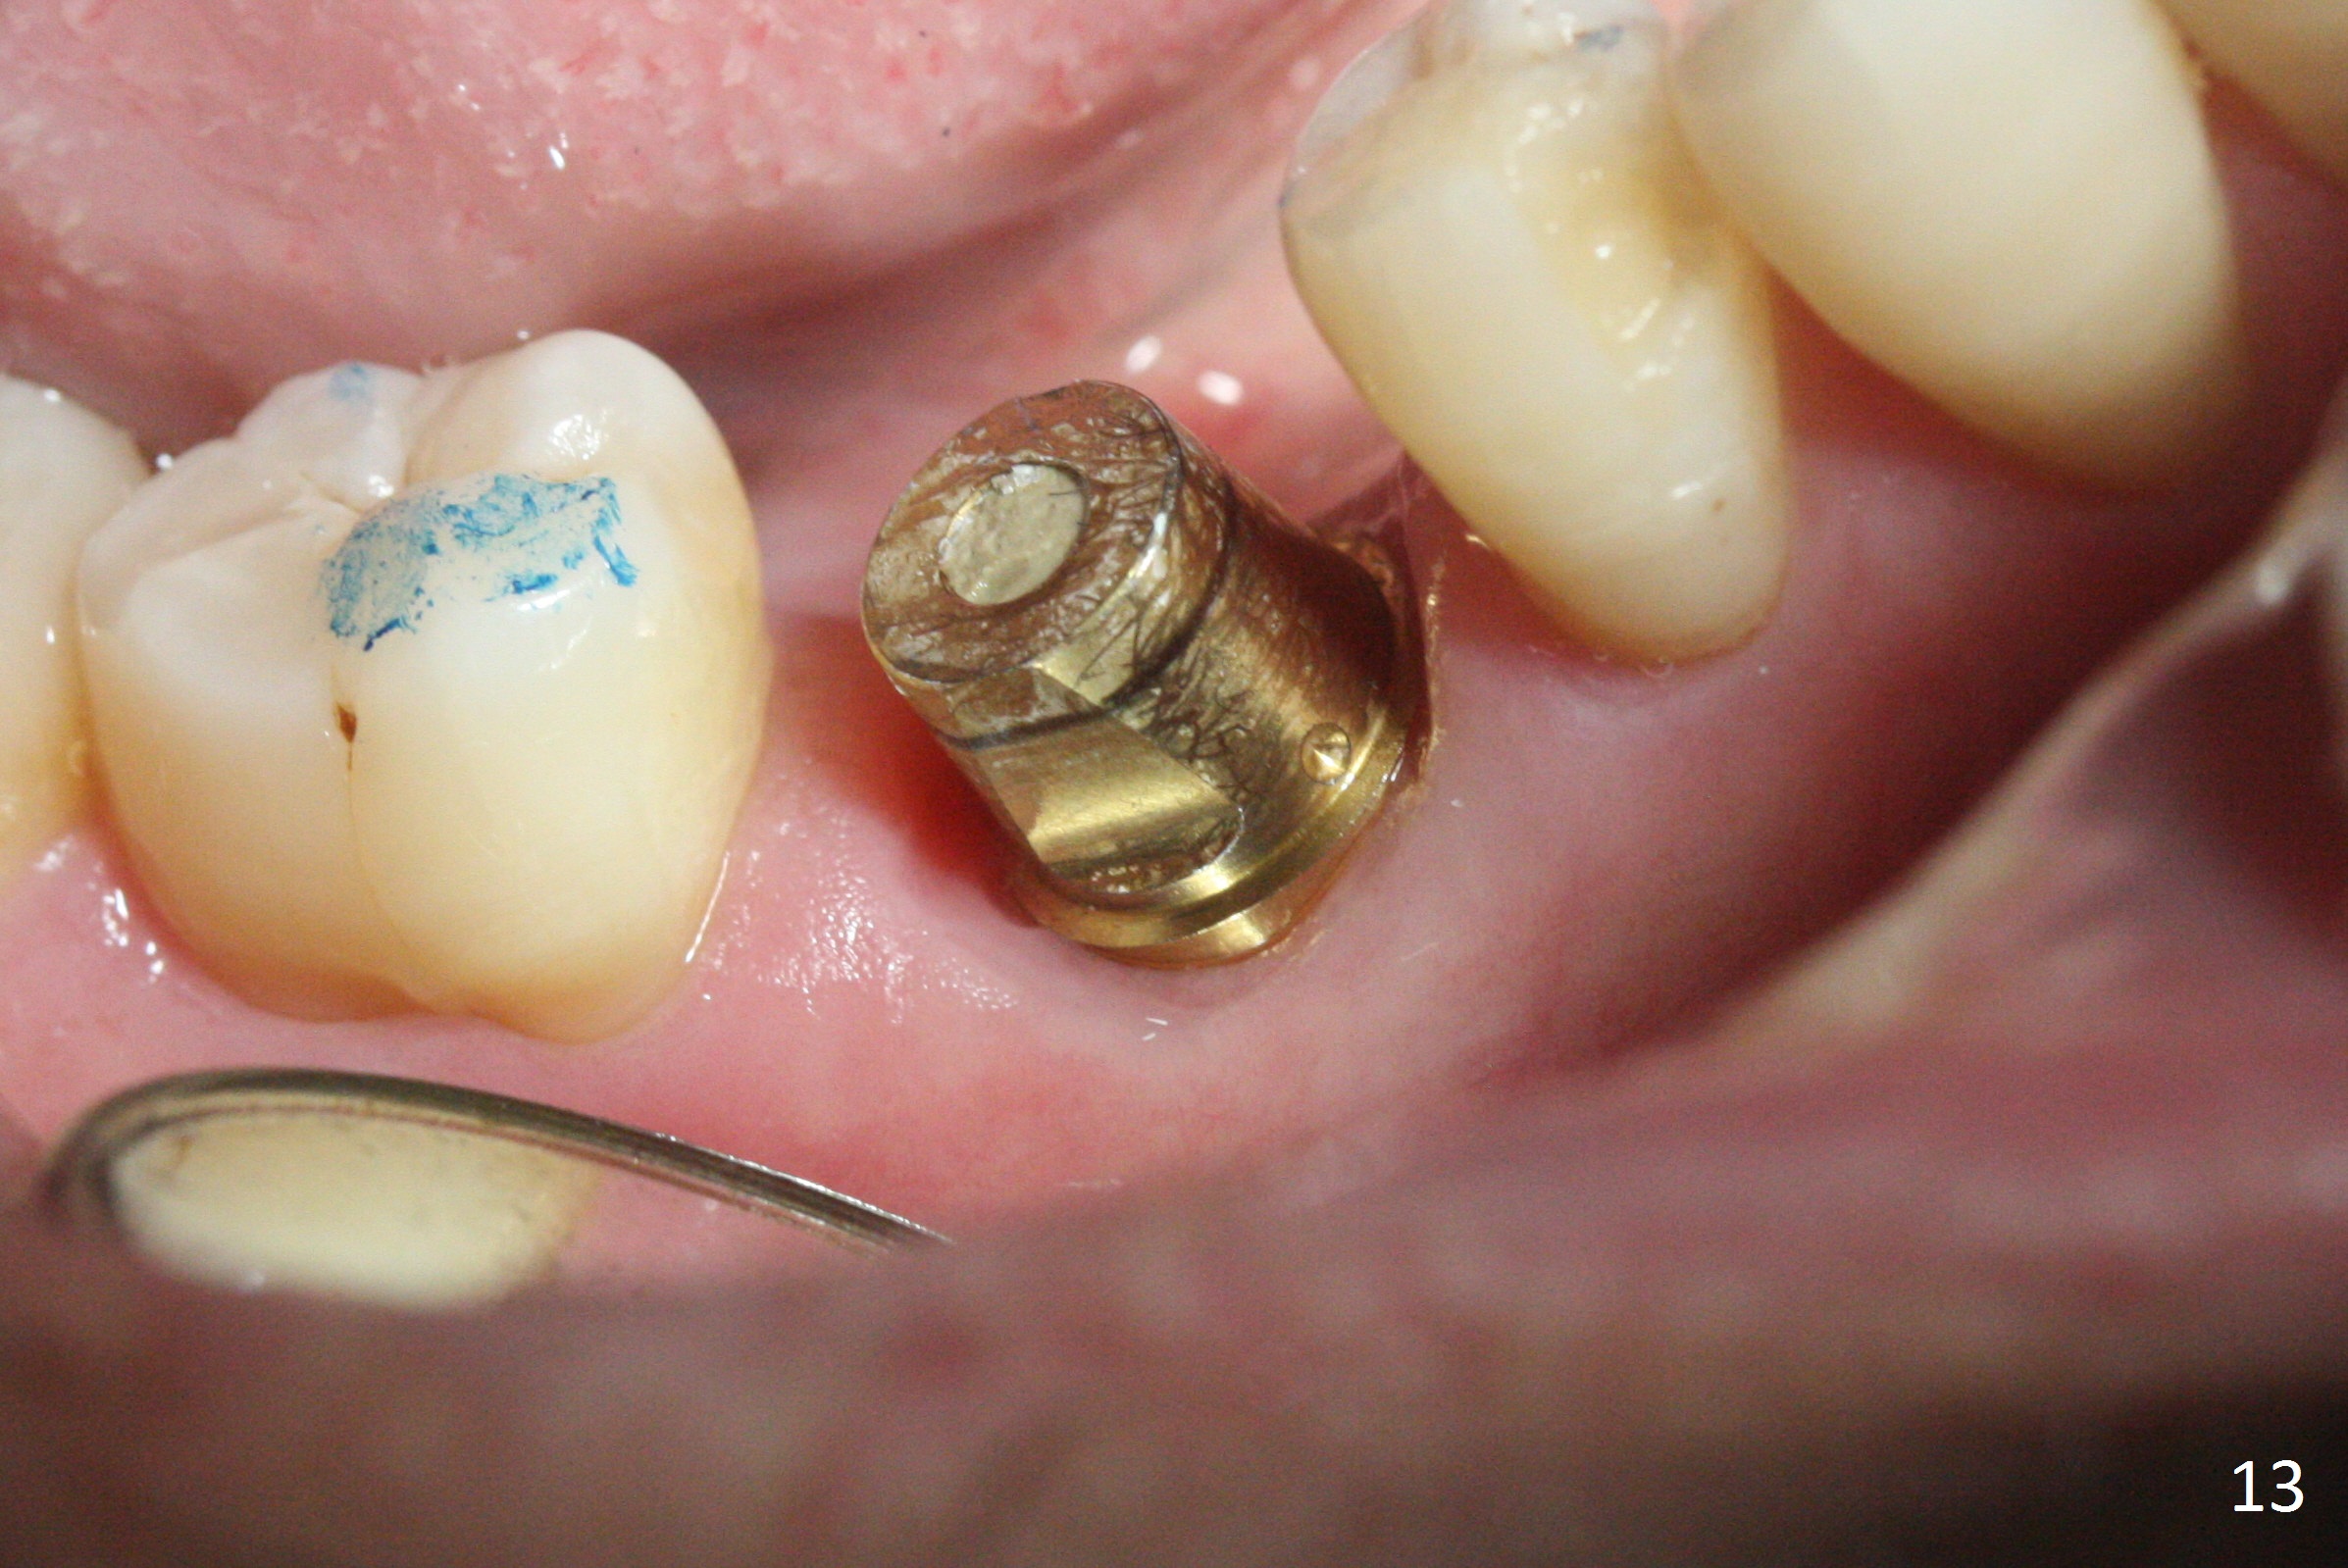

The bone (Fig.10 arrowhead) and soft tissue (Fig.11 *) heal 2 months postop. Gingivectomy is done with Diode prior to impression (Fig.12). The provisional is relined to keep the margin (Fig.13, 2 weeks later) and a permanent crown tries in (Fig.14).